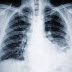

Mesothelioma is a rare cancer that occurs in the tissue covering the stomach and bowels (peritoneal tissue) or in the tissue covering the outside surface of the lung (pleural tissue). 90% of the cases of Malignant Mesothelioma are caused by exposure to Asbestos.

Asbestos is a silicate mineral made up of masses of tiny fibers that are as strong as steel and are highly resistant to heat and chemicals. Fibers of Asbestos are inhaled or swallowed and are able to penetrate to the outside surface of the bowel or to the outside surface of the lung where they become trapped. These trapped fibers can cause a reaction that leads to Mesothelioma Cancer. Mesothelioma symptoms may not appear until about 20 or 40 years from first exposure to airborne Asbestos fibers.

Mesothelioma treatments include radiation to shrink cancer tissue or cells, chemotherapy to stop the reproduction of cancer cells, photodynamic therapy and some times, surgery to remove cancerous tissue.